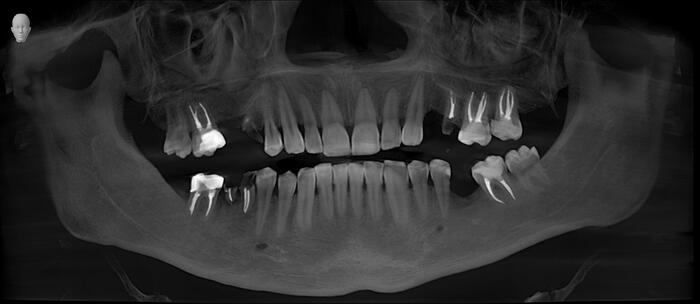

Я подготовился к приему заранее, посмотрел компьютерную томографию, которую он мне прислал.

По снимку видно, что необходим комплексных подход к проблеме, который будет включать в себя мою работу, как хирурга, так и смежных специалистов. Гигиениста, ортопеда и терапевта.

В полости рта ситуация выглядит так:

Отмечается сильная истираемость зубов в связи с длительным отсутсвием полноценного контакта в жевательном отделе.